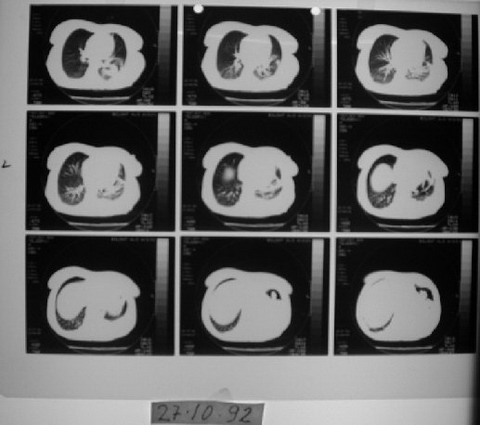

53 yaşında kadın hasta • 9 ayda tam iyileşme

1991 yılında az diferansiye fibröz malign mezotelioma teşhisi konulan 53 yaşındaki kadın hasta, çok düşkün haldeyken immünomodülatör tedavi ile 9 ayda tam iyileşme sağladı. 2000 yılında hasta remisyondaydı ve 9 yıl boyunca hastalık belirtisi göstermedi.

Ödem kayboldu, radyoloji normale yakın

Radyolojik bulgular normale yakın hale gelmişti ve immünomodülatör tedaviyi kesmesi önerildi.